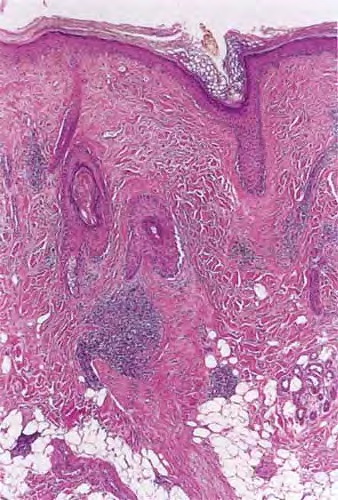

Discoid LE= الذئبة الحمامية القرصية